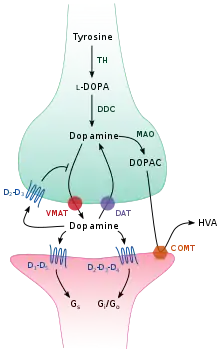

Storage, release, and reuptake

TH: tyrosine hydroxylase

DOPA: L-DOPA

DAT: dopamine transporter

DDC: DOPA decarboxylase

VMAT: vesicular monoamine transporter 2

MAO: Monoamine oxidase

COMT: Catechol-O-methyl transferase

HVA: Homovanillic acid

Inside the brain, dopamine functions as a neurotransmitter and neuromodulator, and is controlled by a set of mechanisms common to all monoamine neurotransmitters.[23] After synthesis, dopamine is transported from the cytosol into synaptic vesicles by a solute carrier—a vesicular monoamine transporter, VMAT2.[36] Dopamine is stored in these vesicles until it is ejected into the synaptic cleft. In most cases, the release of dopamine occurs through a process called exocytosis which is caused by action potentials, but it can also be caused by the activity of an intracellular trace amine-associated receptor, TAAR1.[34] TAAR1 is a high-affinity receptor for dopamine, trace amines, and certain substituted amphetamines that is located along membranes in the intracellular milieu of the presynaptic cell;[34] activation of the receptor can regulate dopamine signaling by inducing dopamine reuptake inhibition and efflux as well as by inhibiting neuronal firing through a diverse set of mechanisms.[34][37]

Once in the synapse, dopamine binds to and activates dopamine receptors.[38] These can be postsynaptic dopamine receptors, which are located on dendrites (the postsynaptic neuron), or presynaptic autoreceptors (e.g., the D2sh and presynaptic D3 receptors), which are located on the membrane of an axon terminal (the presynaptic neuron).[23][38] After the postsynaptic neuron elicits an action potential, dopamine molecules quickly become unbound from their receptors. They are then absorbed back into the presynaptic cell, via reuptake mediated either by the dopamine transporter or by the plasma membrane monoamine transporter.[39] Once back in the cytosol, dopamine can either be broken down by a monoamine oxidase or repackaged into vesicles by VMAT2, making it available for future release.[36]

In the brain the level of extracellular dopamine is modulated by two mechanisms: phasic and tonic transmission.[40] Phasic dopamine release, like most neurotransmitter release in the nervous system, is driven directly by action potentials in the dopamine-containing cells.[40] Tonic dopamine transmission occurs when small amounts of dopamine are released without being preceded by presynaptic action potentials.[40] Tonic transmission is regulated by a variety of factors, including the activity of other neurons and neurotransmitter reuptake.[40]